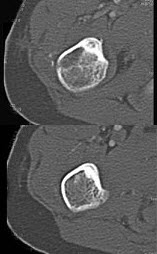

260、单项选择题

男,28岁,右上肢疼痛,夜间加重,服用止痛药可缓解,结合图像,最可能的诊断是()

E.成骨细胞瘤